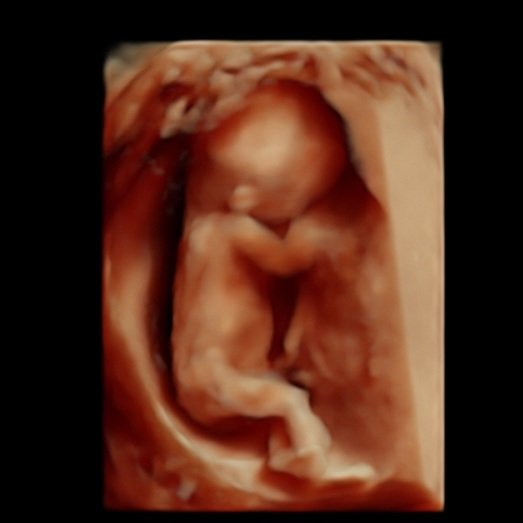

We have the latest ultrasound technology (HD Live) available. We provide you with the clearest 4d ultrasound images and nothing is left to the imagination, here is a reality, you will see your baby's movements in real time. We have some of our babies' images in our gallery so you might look according to your gestational age and get an idea of how you will see your baby. Please scroll down this page for more samples of our before and after baby pictures. They will give you a better idea of what are you getting when you book a 3D/4D/HD Live ultrasound session with Preggoland. We cannot wait to enjoy this unforgettable experience with you!

12 to 18 Weeks

Graphical explanation of how the babies are looking according to the gestational age. All 2D, 4D & HD Live images featured here have been taken by Preggoland. Please use them as a reference for your booking, from 12 weeks of pregnancy to 18/19 you can get beautiful full-body pictures & videos, your tiny human is growing fast. Don’t miss the opportunity to watch your baby’s development.